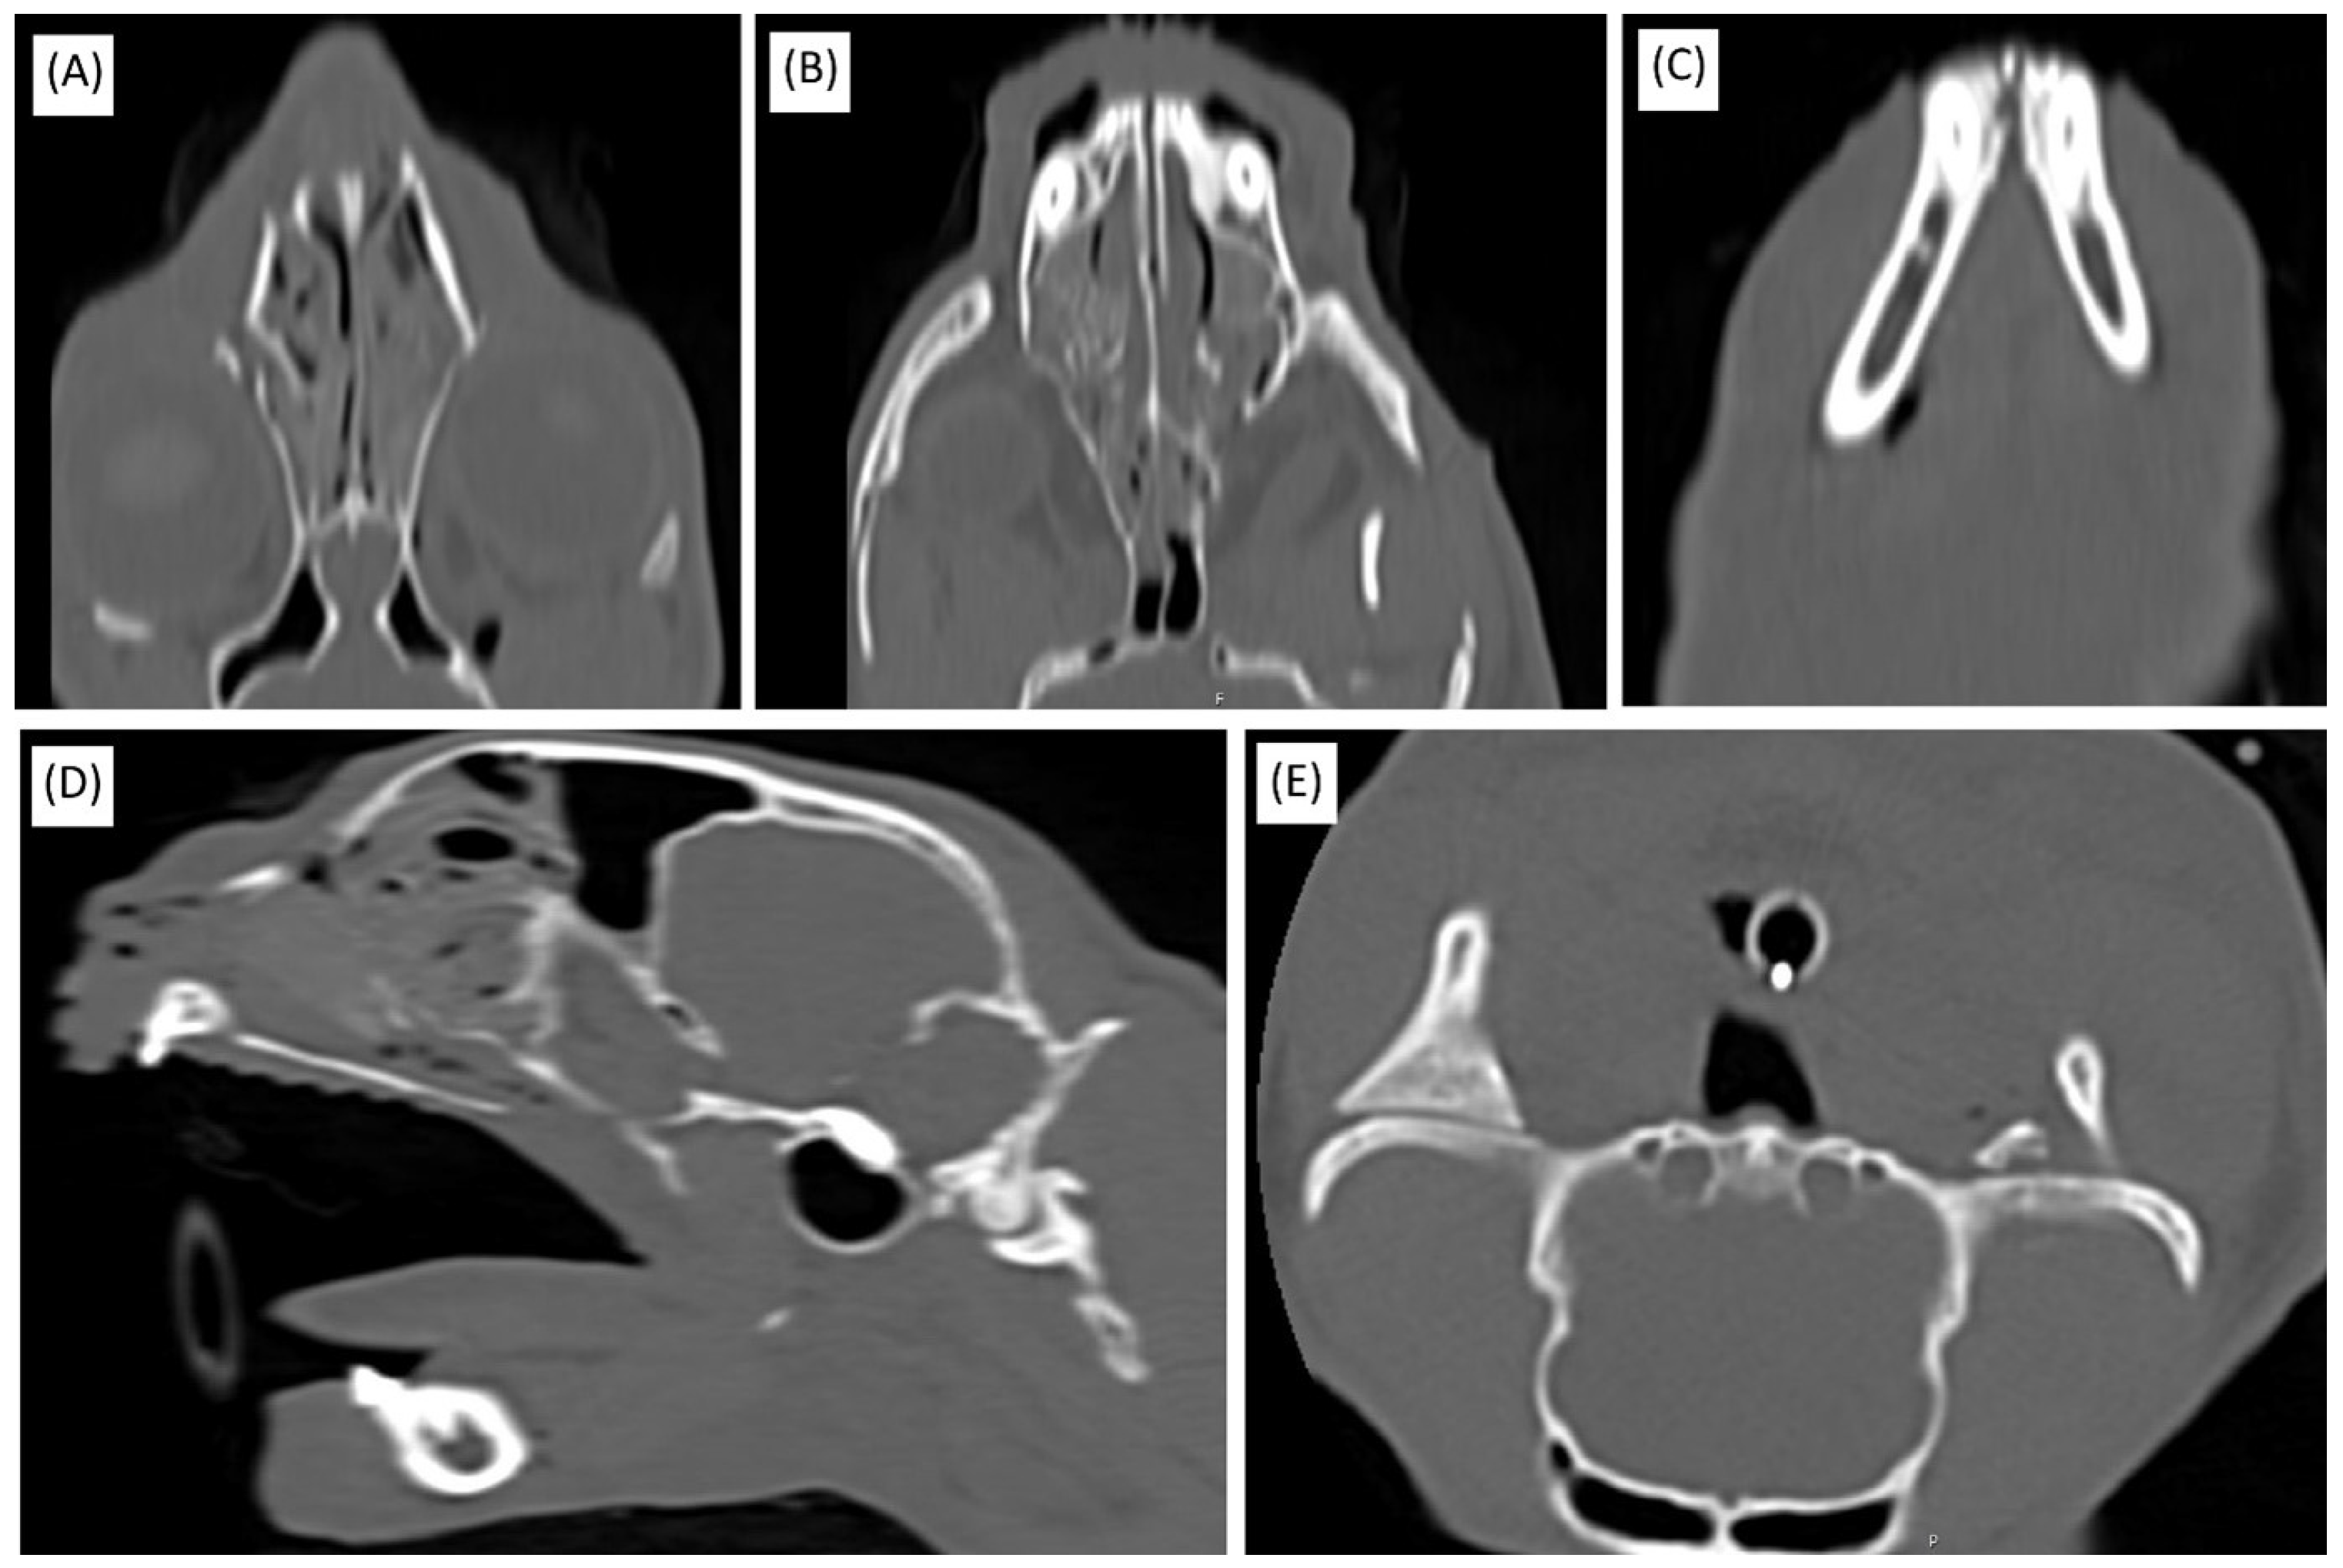

Considering the presence of multiple surgical sites and the patient’s critical condition—characterized by loss of consciousness and respiratory failure—optimized surgical strategies were adopted to minimize the procedural time and prevent further deterioration. Although time-consuming, computed tomography (CT) imaging was deemed indispensable for the accurate evaluation of craniofacial trauma and the formulation of a precise surgical plan. CT imaging confirmed extensive injuries involving multiple fractures and soft tissue compromise, necessitating prompt surgical intervention (Figure 1). Fortunately, no damage to individual teeth was identified upon visual inspection, palpation, or CT imaging.

Figure 1. Diagnostic CT imaging of the skull. (A) Coronal view displaying the left maxilla/orbit fracture. (B) Coronal view highlighting the bony palate fracture. (C) Coronal view showing the mandibular symphysis fracture. (D) Sagittal view illustrating hemorrhagic exudate within the nasal cavity. (E) Axial view depicting the left temporomandibular joint (TMJ) luxation.